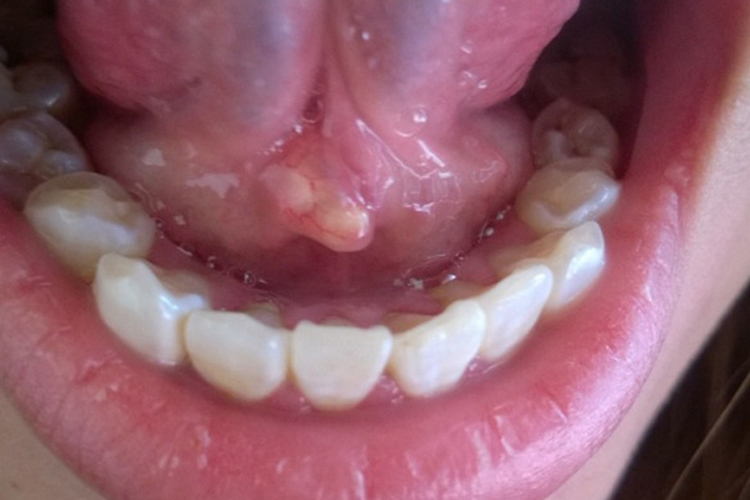

尖锐湿疣

初期表现为局部细小丘疹,针头至绿豆大小,逐渐增大或增多,向周围扩散、蔓延,渐发展为乳头状、鸡冠状、菜花状或团块状赘生物。损害可单发或多发,颜色可为灰白色,表现为舌系带上出现白色疙瘩。